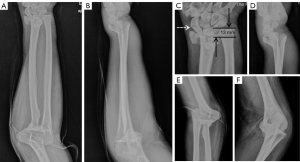

All cases were evaluated by X-ray and computed tomography (CT) examinations on the wrist and elbow joints before operation (Figures 1,2). Fractures classifications of the 13 patients are shown in Table 1. The radial head fractures were categorized based on the Mason classification, including 1 case of type I, 7 cases of type II, and 2 cases of type III. There were 2 cases that were combined with radial neck fractures.

Follow-up outcome

According to the MEPS scoring system, 8 cases were excellent, 3 cases were good, and 2 cases were good. The combined excellent and good rate was 84.6%. According to the MMWS scoring system, 5 cases were excellent, 5 cases were good, and 3 cases were good. The combined excellent and good rate was 76.9%. There were no significant restrictions on elbow and wrist movements (Figure 4). The DASH score was excellent, with an average of 18.5 points.